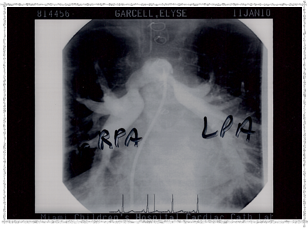

Second Catheterization — Dr. Danyal Khan

In 2010, Elyse underwent her second catheterization procedure, overseen by Dr. Danyal Khan at Miami Children's Hospital. The procedure focused on her pulmonary arteries, and these images show the before and after.

2010 - Left Pulmonary Artery After

Left Pulmonary Artery — After